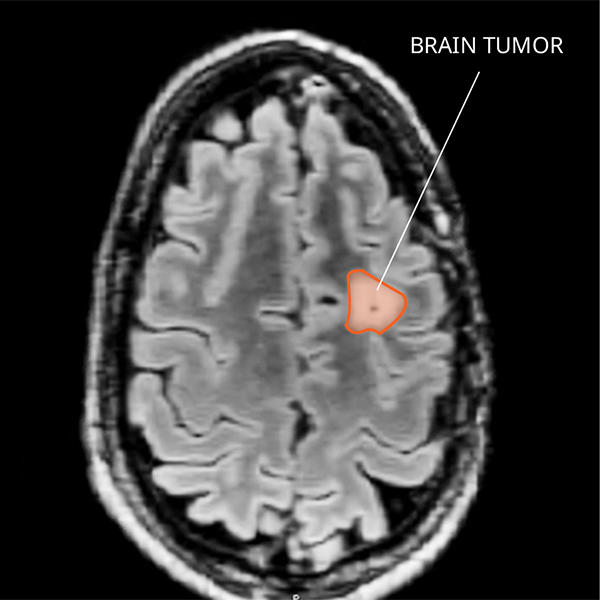

What Do PXAs Look like on an MRI?

PXAs often form fluid-filled cysts within solid tissue, which have a dense appearance on a magnetic resonance imaging (MRI) scan. The way grade 3 PXAs look varies and makes it difficult to tell them apart from other primary CNS tumors. Diagnosing PXAs can’t be done by imaging alone, because they may look similar to glioblastomas and other high-grade brain cancers.